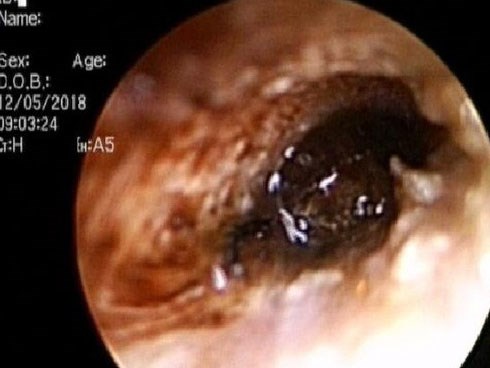

Bé trai 9 tuổi đang ngủ bị 'vật thể lạ' chui vào tai suýt thủng màng nhĩ

Bé trai đang ngủ thì tai phải đau dữ dội kèm nhức đầu, chảy máu. Đưa đến bệnh viện cấp cứu, các bác sĩ thăm khám và phát hiện một "vật thể lạ" vô cùng nguy hiểm.